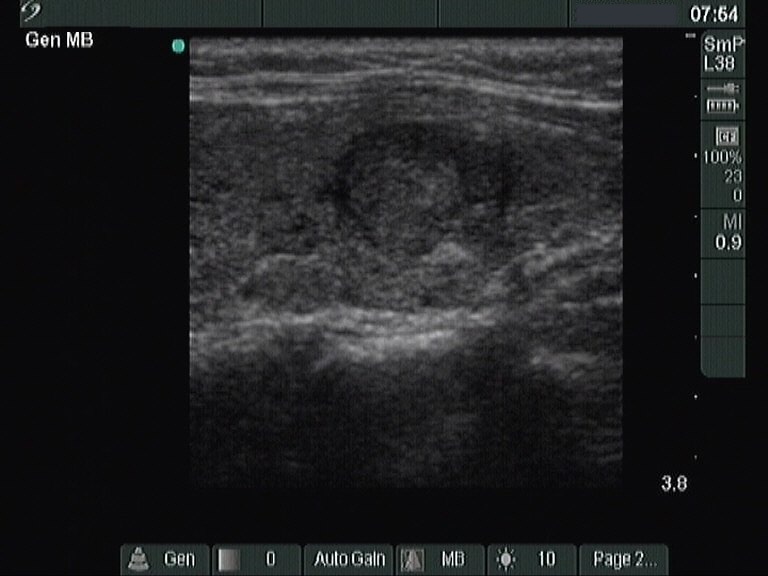

Papillary carcinoma - Case 26. (ultrasonographic picture 5)

Left lobe, longitudinal scan.